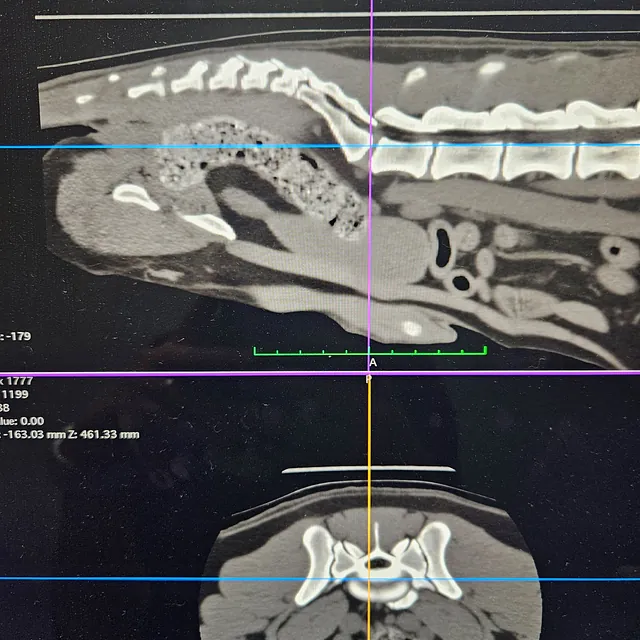

CT Scanner

Our CT scanner was installed at our Tunstall practice in 2017 and was the first permanent veterinary CT scanner in our area. It is available 24 hours a day to both our own patients and as a referral service to surrounding practices.

Computed Tomography (CT) involves the use of x-rays to take thousands of pictures of cross-sections of the body. These can then be built up into a 3D image and used to create a detailed reconstruction of the patient. This is a thorough and prompt way to reach a diagnosis and enable quicker treatment. The CT scanner is particularly useful for the diagnosis and planning of complex surgical procedures and medical conditions.

We are able to obtain full results from external specialists and also, we are lucky that one of our own vets - Charlie Green - is an Advanced Practitioner is Diagnostic Imaging and a General Practitioner in CT; meaning she can read our CT scans on site and enhance surgical planning and treatments.

Brian’s CT Scan

The first CT scan we carried out was done on Clive's dog, Brian's, nose. We found a sarcoma in his upper jaw, and successfully removed it. A CT was needed to ensure the surrounding area was in good health.